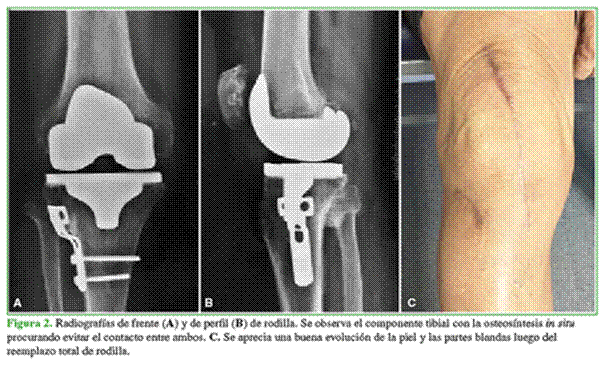

Se utilizaron vástagos tibiales en siete casos con la finalidad de sobrepasar la zona de debilidad generada por la OTA (Figura 3). Además, se colocó un vástago en un paciente con retraso de la consolidación en el sitio de la OTA y en otro con un valgo severo de 25° en el que se utilizó una prótesis constreñida.